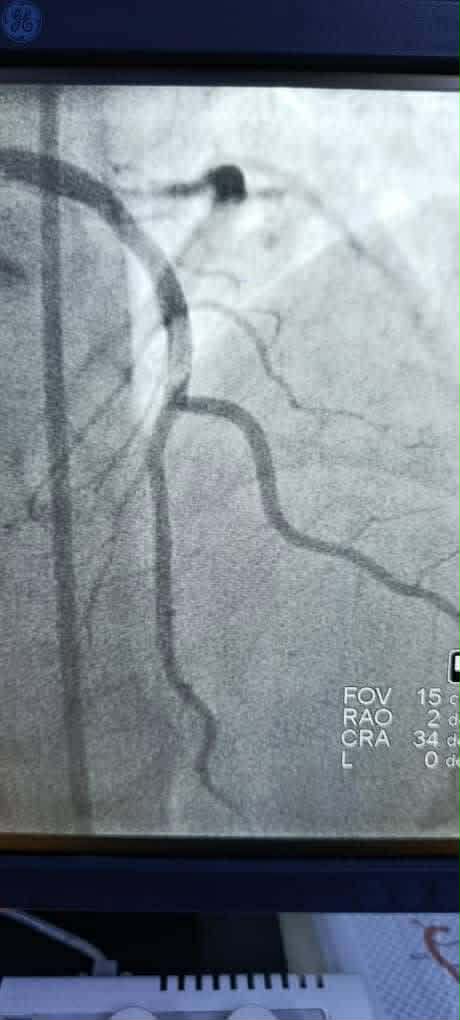

الثانية: مريض في الأربعينات راجع بخناق صدر شديد، مع تاريخ عائلي حافل بالأزمات القلبية والوفيات القلبية. تم فتح الشريان الهامشي المسدود تمامًا باستخدام تقنية “Kissing stent” على تفرع الشريان المنعكس الأساسي، تلاها تحسن ملحوظ في الحالة العامة واستقرار الألم الصدري.

الثالثة: مريض في الخمسينات يعاني من احتشاء أمامي حاد لم يستجب للعلاج الخثاري. تم فتح الشريان الأمامي الرئيسي المسدود تمامًا، وإعادة التروية بشكل جيد.